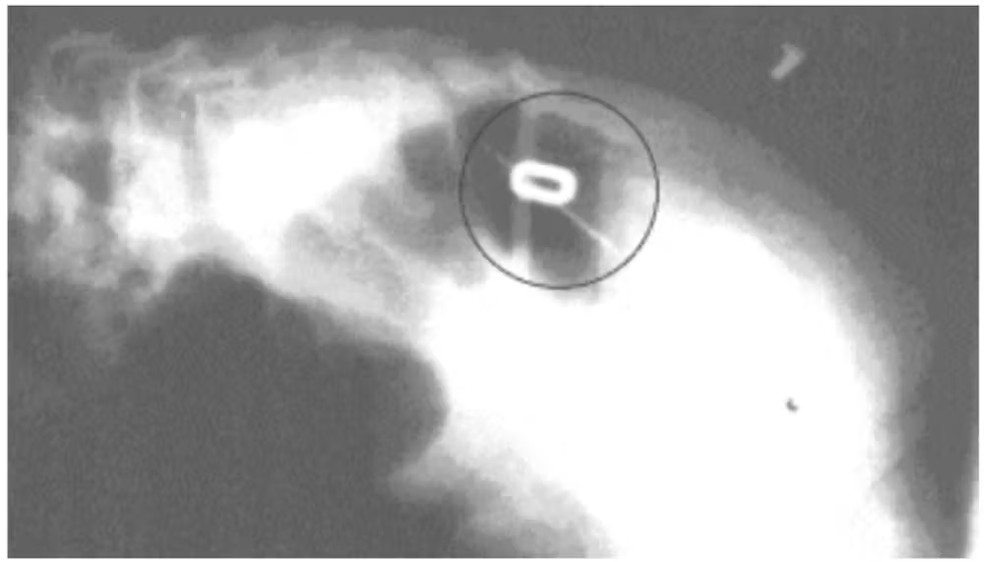

Radiografia feita do primeiro paciente, antes do procedimento cirúrgico. Após nossa análise, dois marcadores, em forma de 0 e 1, foram fixados sobre a pele da criança — Foto: Acervo dos pesquisadores Afinal, ainda havia muito a aprimorar. Apesar da elevada exatidão de nossa técnica, o sensor precisava operar em temperaturas muito baixas, o que encarecia o equipamento, tornava complexa sua operação e dificultava sua fabricação. Isso acabou inviabilizando sua adoção em larga escala como dispositivo biomédico.